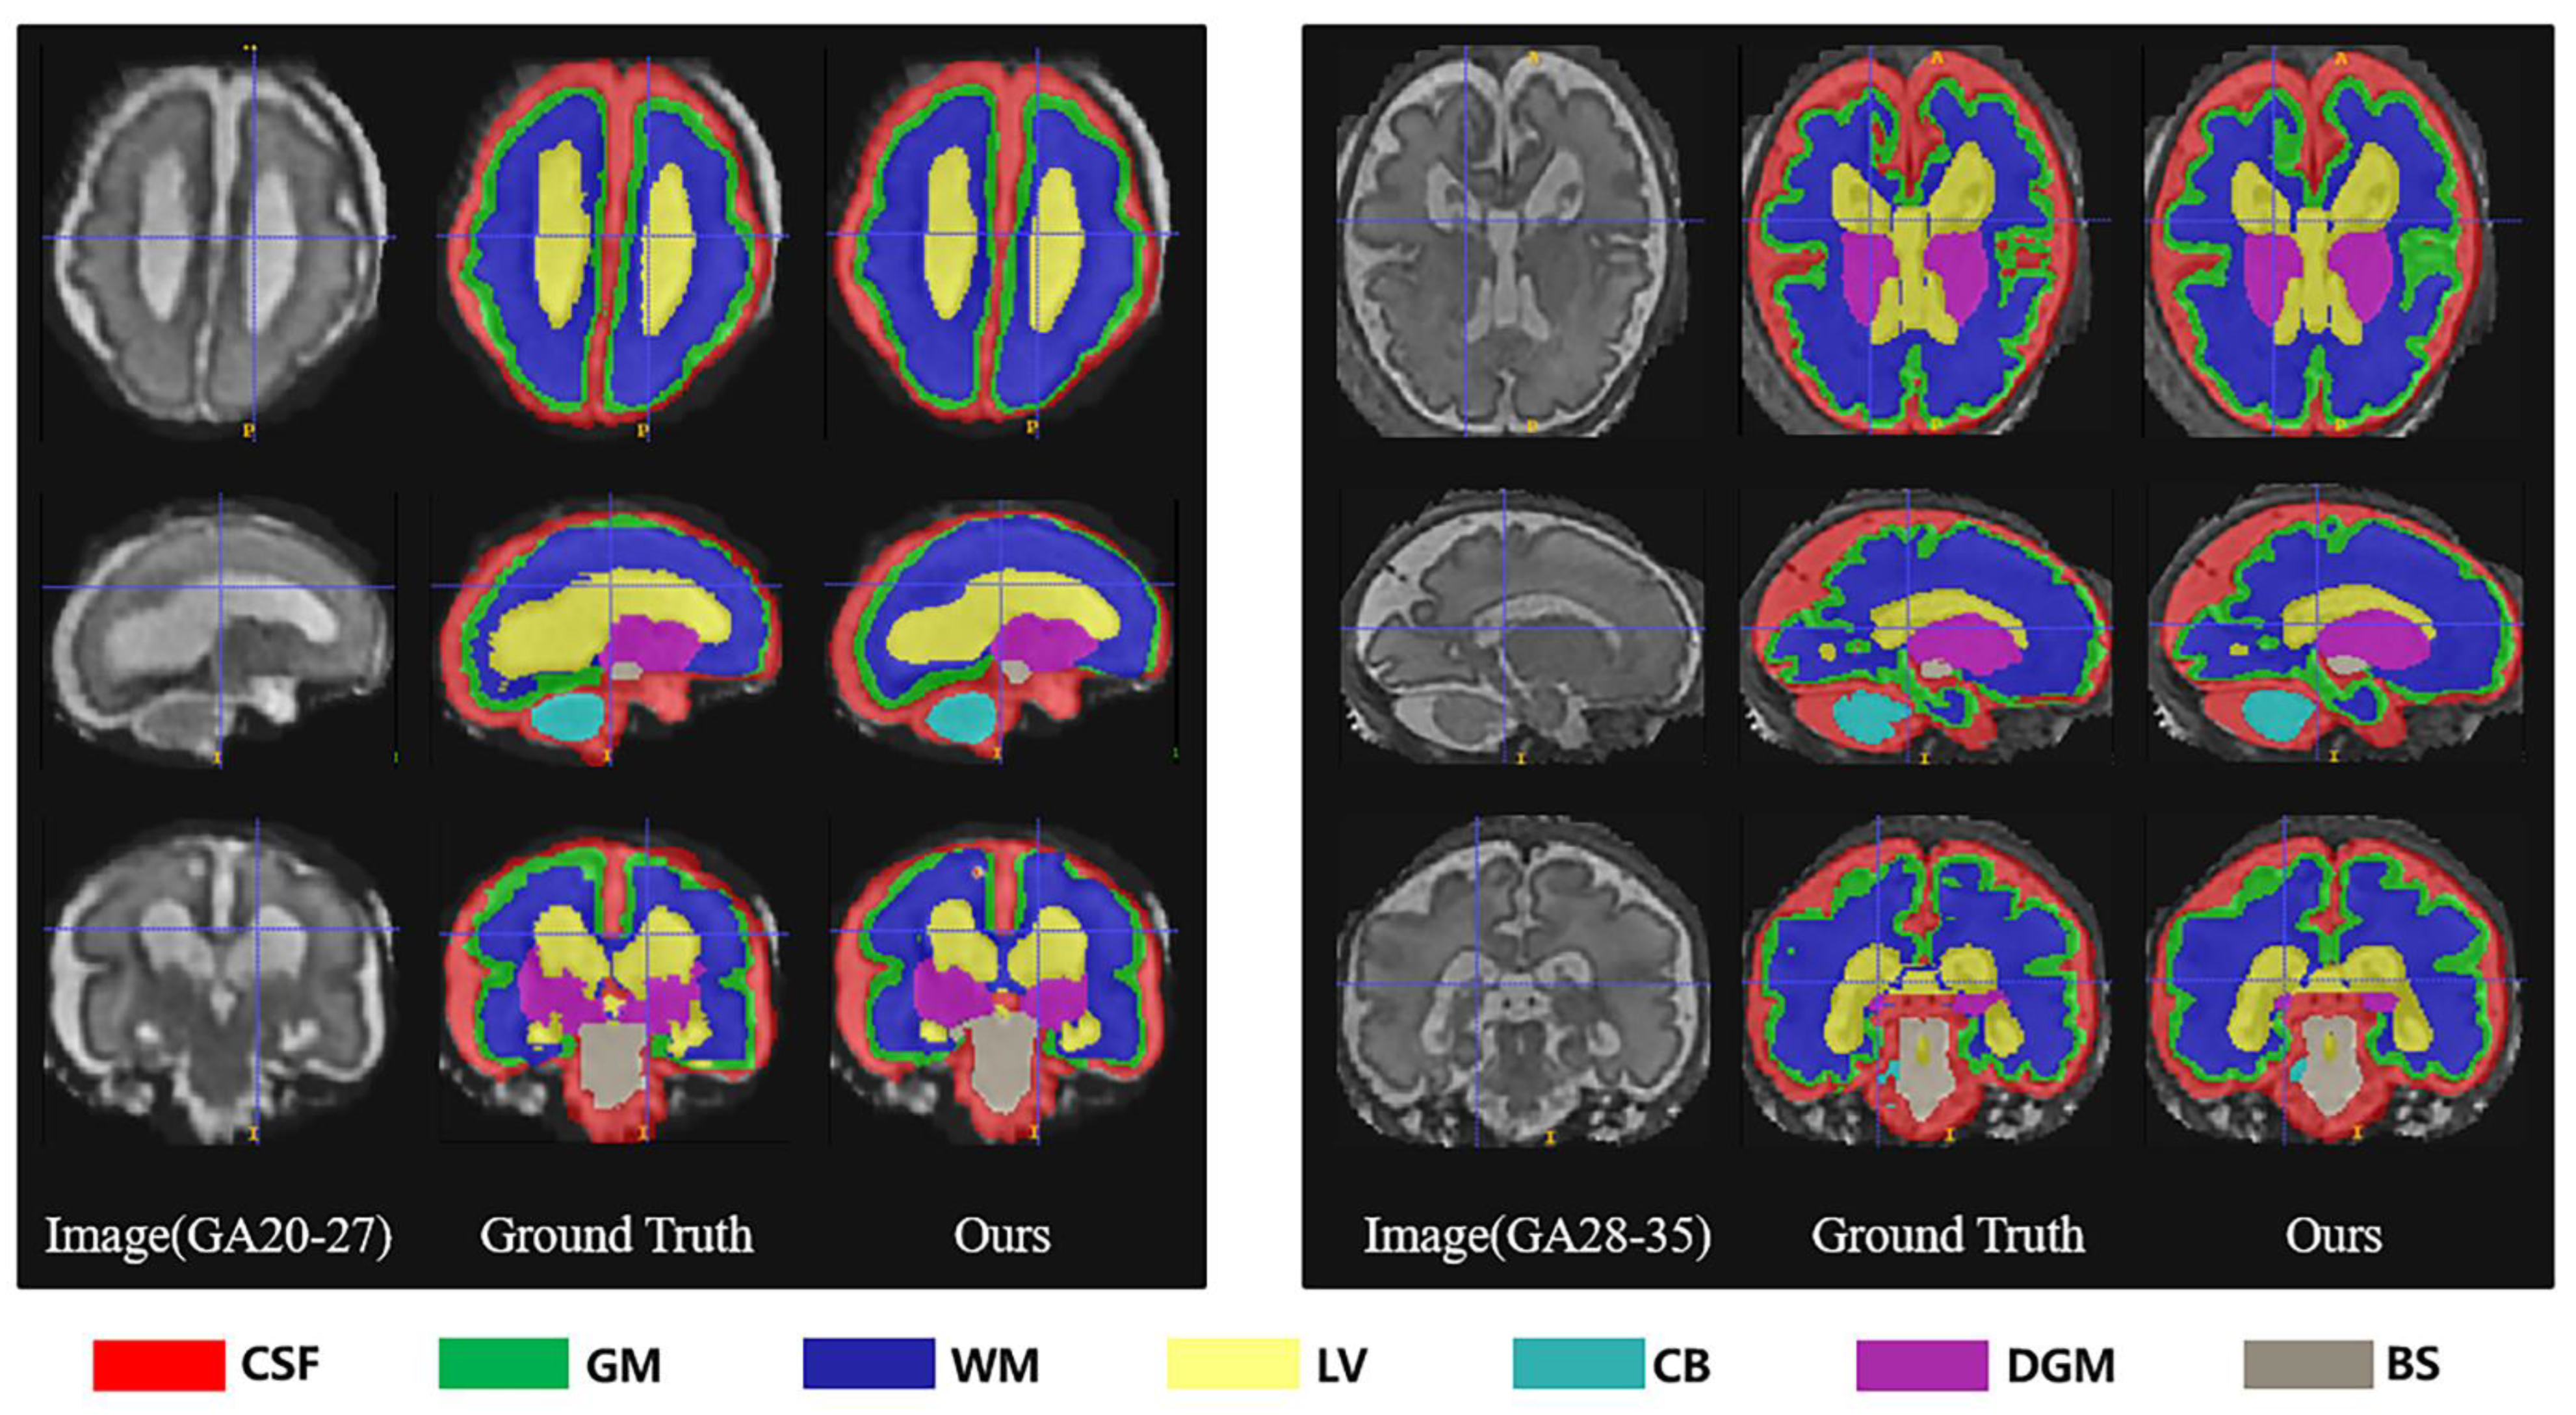

Table 3 showed the evaluation results of several metrics for two different gestational age groups (20–27 GW and 28–35 GW) as a way to analyze the effect of gestational age on the performance of our segmentation algorithm. The results obtained in the table showed that in the 28–35-week group, the segmentation performance of both gray matter and white matter became worse, with a significant decrease in DSC, VS, PRE, and SEN and an increase in HD95. The segmentation of the lateral ventricles was also poorer in the 28–35-week group. This supported our hypothesis that segmentation was more difficult due to the decrease in ventricle-to-brain volume ratio with increasing gestational age. Overall, the 28–35 age group showed a slight increase in segmentation difficulty compared to the group of 20–27 GW, with a 2.15% decrease in mean DSC (%) from 89.88 to 87.95 and a 1.98% decrease in VS (%) from 91.58 to 89.77. We also provided a few examples for visual comparison of the two age groups in Figure 7. The cerebral cortex expanded with increasing gestational age, and the morphology of the cerebral gyri and sulci became more notable. Discernibility of the gray/white matter boundary became variable in some regions due to partial volume effects produced by gyri. Gray matter (green) segmentation became more indistinguishable from cerebrospinal fluid (red) and white matter (dark blue) boundaries. In the 28–35 GW group, the volume of ventricles (yellow) became significantly smaller and the shape changed, and it was no longer simply vesicular or bicornuate, which also led to an increase in the random error of segmentation.

Table 3.

Comparison of segmentation results of different gestational age groups (20–27 weeks and 28–35 weeks) based on quantitative performance metrics (DSC, VS, HD95, PRE, SEN, SPC).

Figure 7.

Segmentation results of different gestational age groups (20–27 weeks and 28–35 weeks) in axial, sagittal and coronal planes respectively.